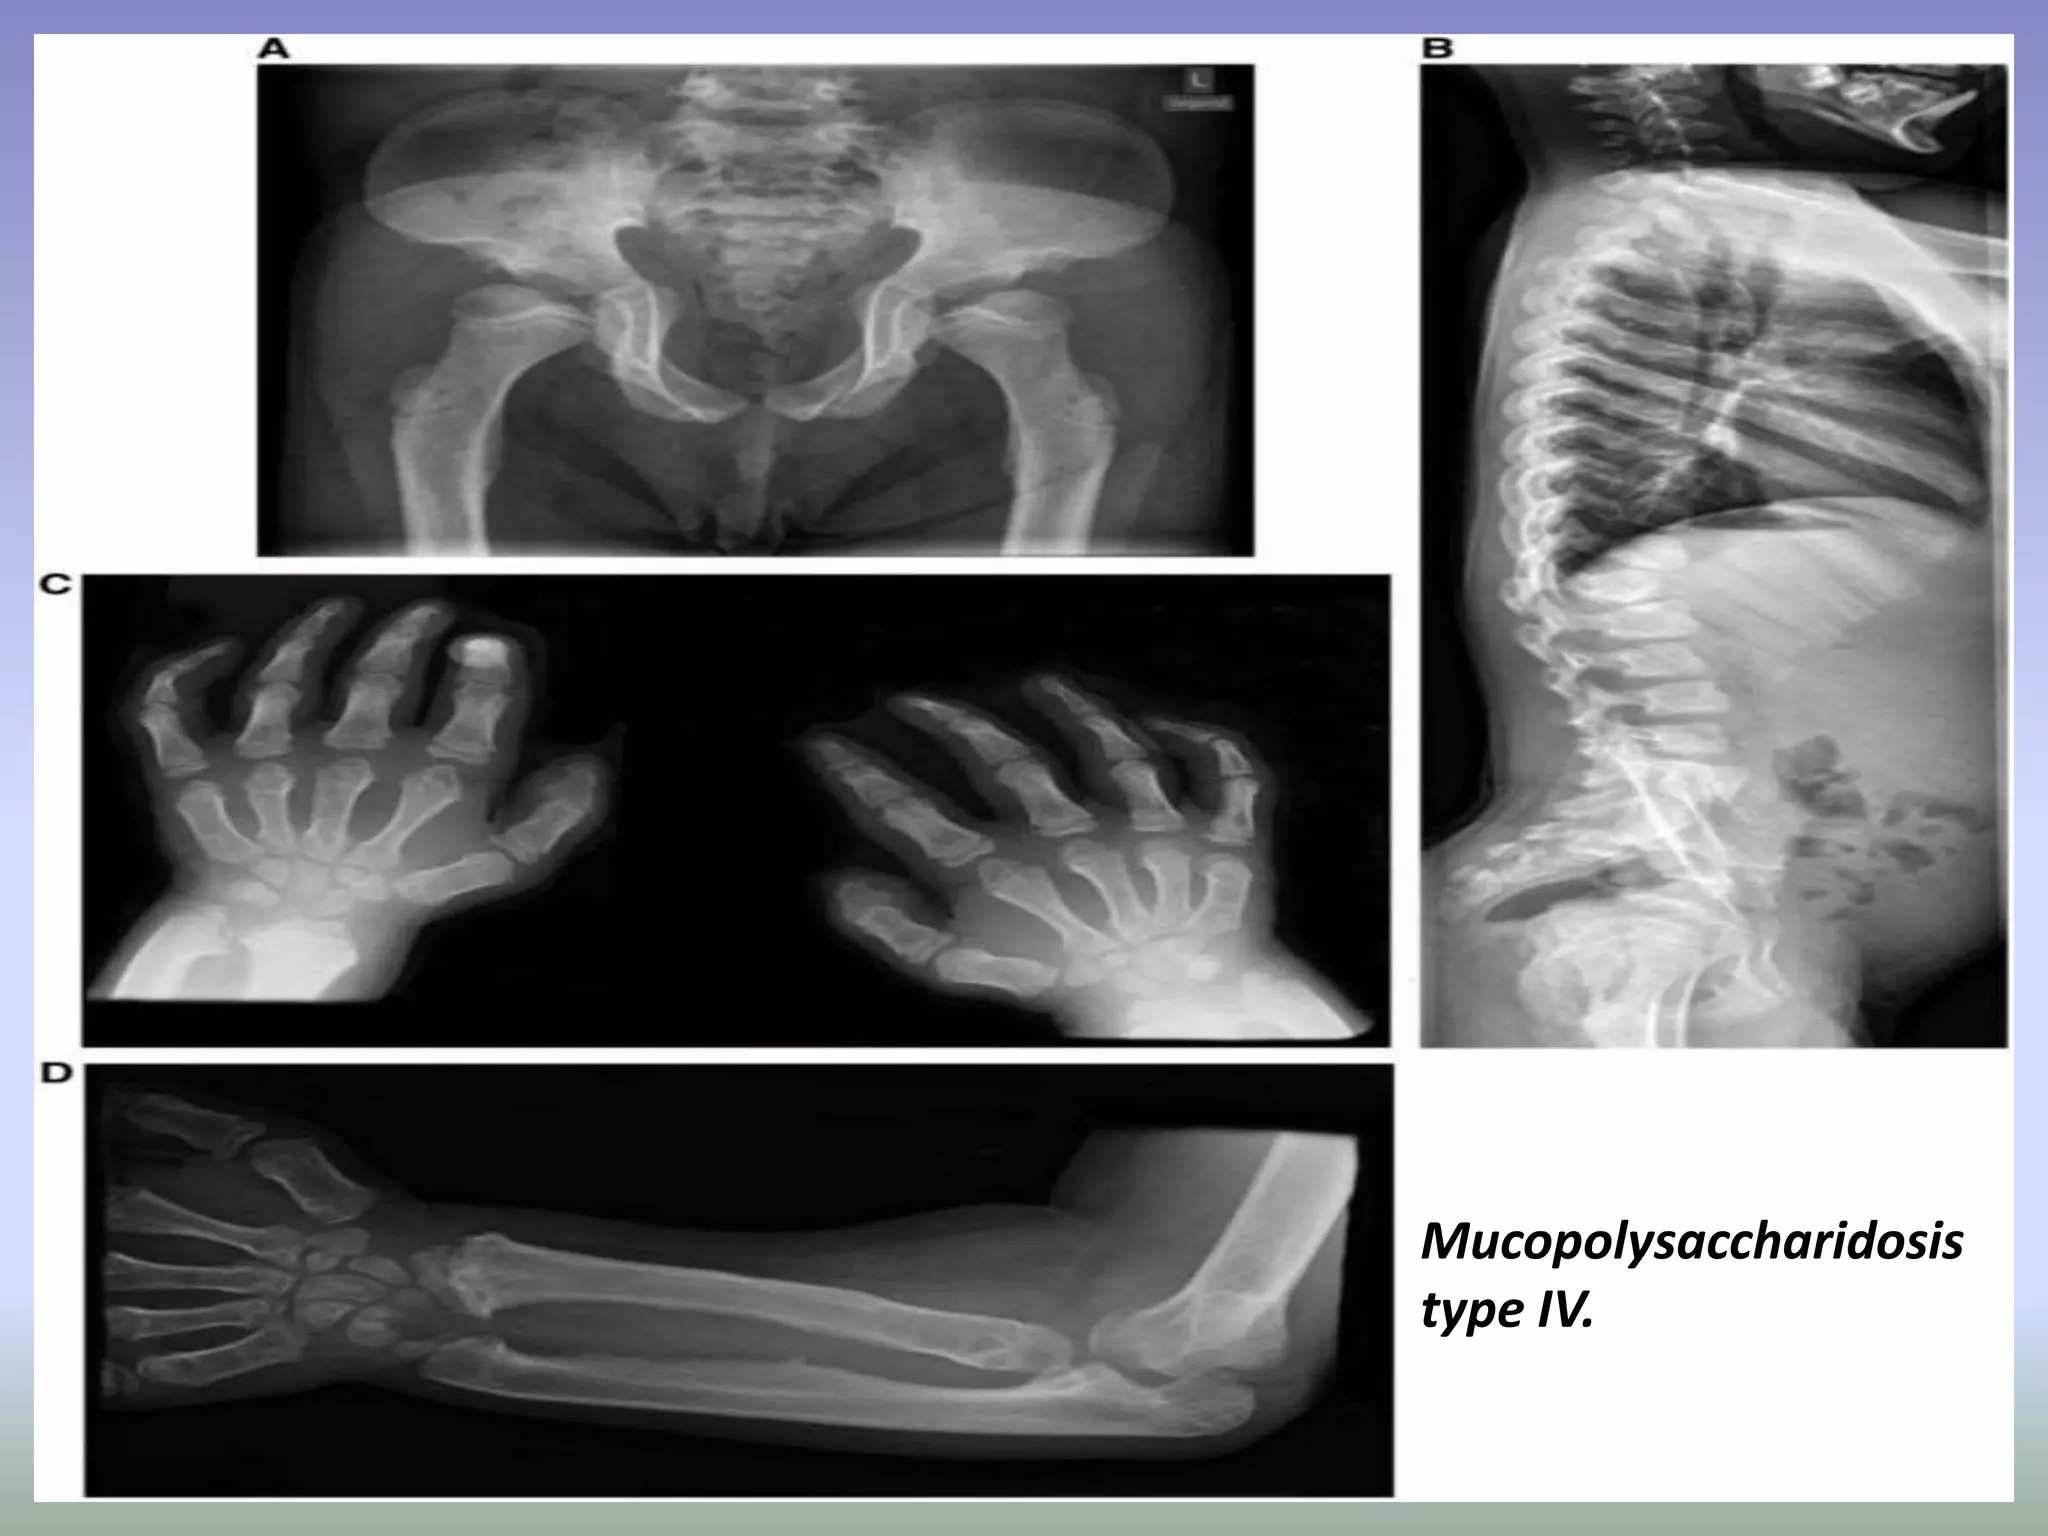

Mucopolysaccharidosis

type IV.

MPS IV